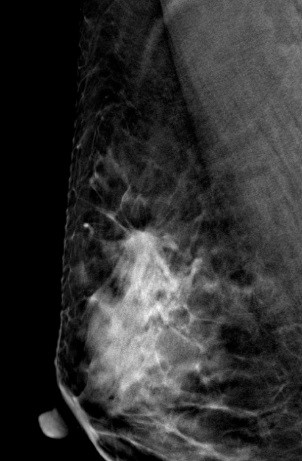

病史:患者43岁,发现右乳包块2周。

V-preview图像:

DBT图像:

常规2D图像MLO位上象限见一团块状影,在CC位上并没有发现可疑异常密度影,在V-Preview图像和tomo图像上我们可以清楚发现病变边界不清见长短不一毛刺,呈星芒样改变。

右乳上方略偏外局限致密影BI-RADS 4B 。

在TOMO图像上对星芒样病灶周边情况显示明显优于2D图像,最后病理证实右乳浸润性导管癌。